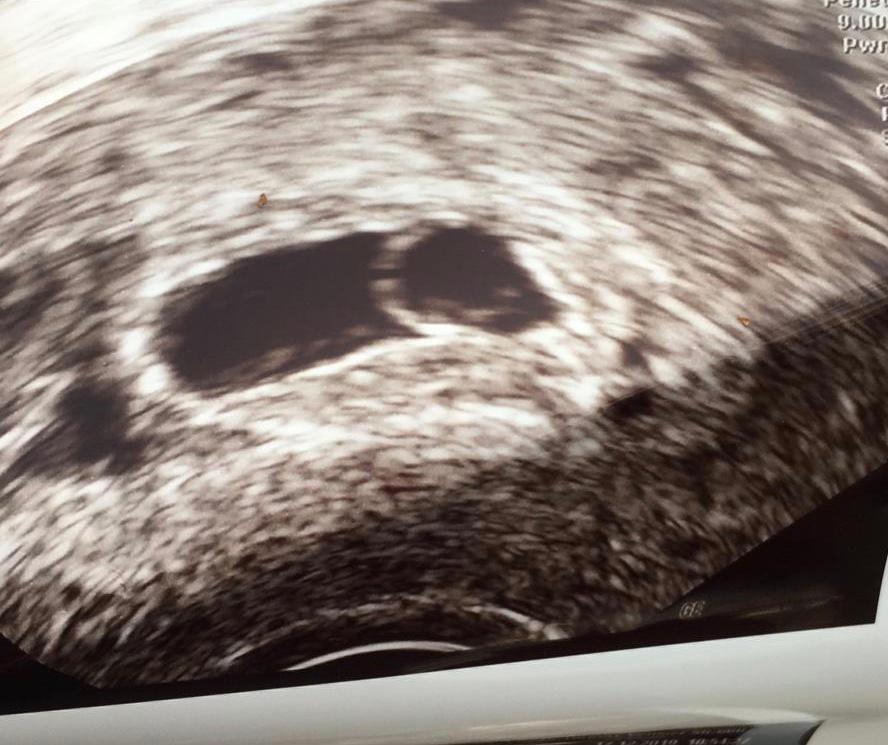

Dann hat sie Ultraschall gemacht und es war natürlich noch nix zu sehen (bei meiner ersten SS war Anfang der 6SSW noch nicht mal eine Fruchthöhle zu sehen), sie hat einen dunklen Fleck entdeckt, welcher evtl eine Fruchthöhle sein könnte, aber sicher können man da nie sein. 6ssw im Ultraschall ist nichts zu sehen Seite 2 Ich war gestern im KH weil ich Unterleibsschmerzen hatte, die netter Ärztin hatte mich untersucht und festgestellt, dass ich ein wenig Wasser im Bauch habe, was auf eine Eileiterss hindeuten kann Sie hat mir auch ein Dottersack gezeigt mit einem kleinen weißen Punkt an der linken Seite Sie hat aber gesagt dass das baby noch nicht. Hallo, die Situation ist in den heutigen en leider so, dass die Schwangerschaftsteste immer früher durchgeführt werden und diese dann auch entsprechend früh anschlagen Dieses bringt dann aber häufig mehr Verwirrung, Unsicherheit und zusätzliche Diagnostik mit sich, als einem lieb sein kann.

Die Fruchthöhle ist schwarz und deutlich auf dem Ultraschall zu sehen Da durch einen Ultraschall in der 3 Schwangerschaftswoche kein Ergebnis zu sehen ist und die meisten werdenden Mütter noch nichts von einer möglichen Schwangerschaft ahnen, wissen sie es aber ab der 4 SSW, wenn die cm 6'44 cm In der 6. Hier ist der Dottersack nun sehr deutlich zu sehen (man sieht hier auch, wie wichtig die Qualität der Ultraschallgeräts sein kann Der Dottersack wurde hier vermessen und hat einen Durchmesser von 3 Millimetern Der Embryo ist auf diesem Bild noch nicht davon abgrenzbar Ultraschallbild 56 SSW Ein Ultraschallbild vom 6 der 6. Deine vermeidlich 6SSW Ultraschalluntersuchung kann sich also als ein Flopp herausstellen, da man auf dem Ultraschall noch gar nichts sieht Es kann nämlich sein, dass du erst in der 5Schwangerschaftswoche bist, da dein Eisprung erst ein oder zwei e später war oder die Einnistung der befruchteten Eizelle an deiner Gebärmutterwand erst.

6ssw im Ultraschall ist nichts zu sehen Ich war gestern im KH weil ich Unterleibsschmerzen hatte, die netter Ärztin hatte mich untersucht und festgestellt, dass ich ein wenig Wasser im Bauch habe, was auf eine Eileiterss hindeuten kann Sie hat mir auch ein Dottersack gezeigt mit einem kleinen weißen Punkt an der linken Seite. Antwort auf Im Ultraschall nichts zu sehen, eigentlich 6SSW Hallo Julia, da Frauen, wie Sie leider immer früher in der Praxis nach positivem Schwangerschaftstest erscheinen, um die Schwangerschaft im Ultraschall nachweisen zu lassen, finden wir diese Situation auch immer häufiger In dem Moment können wir aber nur auf die Verlaufskontrolle verweisen, die klären kann, ob es noch zu. SSW und auf ultraschall noch nichts zu sehen 6 SSW und auf ultraschall noch nichts zu sehen Kes 2 Beiträge 2616 1506 Mein FA bestätigte mir gestern eine Schwangerschaft in der Woche 60 Auf dem ultraschall war aber leider noch gar nichts zu sehen jetzt mach ich mir natürlich Gedanken um eine Eileiterschwangerschaft.